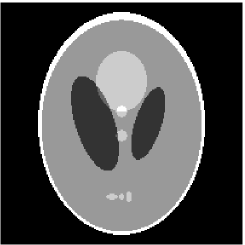

Furthermore, we used the classic ART iteration as the iteration operator in our numerical experiments. In order to compare the proposed superiorization algorithm with the classic superiorization algorithm, we applied the classic superiorization and -PP superiorization algorithm to two phantoms (see figure 1). The first one is the Shepp-Logan phantom[30], and the second one is the head phantom with a ghost which is invisible at 22 specified projection directions [10, 31]. In addition, we compare the performances of the two algorithms for the noiseless and noised data with different projections. In all experiments, the noised projection data was corrupted by additive Gaussian white noise with variance . We record the iterations, running time of program and mean square error (MSE) of different algorithms, where MSE is computed by

3.1 Shepp-Logan phantom

Noiseless projection data: The projection data were collected by calculating line integrals across the phantom at 60, 90, 120 directions(equal increments and from to ) of 201 equally spaced parallel lines from to . Iteration procedures were terminated when for the noiseless experiments.

The reconstruction images from the noiseless projection data were shown in the Fig. 2. From Fig. 2, we can observe that the classic and the proposed algorithms can reconstruct images from the three projection data. In order to show the advantages of the proposed algorithm visually, the central vertical line of the differences between the reconstructed images and the original image are present in Fig. 3. We can observe that the -PP superiorization is more efficient than the classic superiorization in the aspect of suppressing the artifacts in the reconstructed images.